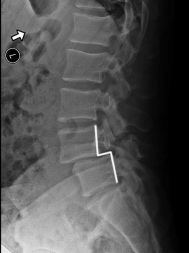

When we look at the spine from the side, we can imagine a scotty dog. It is outlined above. The pars fracture is seen as a collar around the dog's neck. Instability and movement can cause the neck to widen. We will see this below in an X-ray example.

X-RAY SHOWING A PARS FRACTURE DEFECT

THE WHITE OUTLINE SHOWS THE SLIPPAGE.